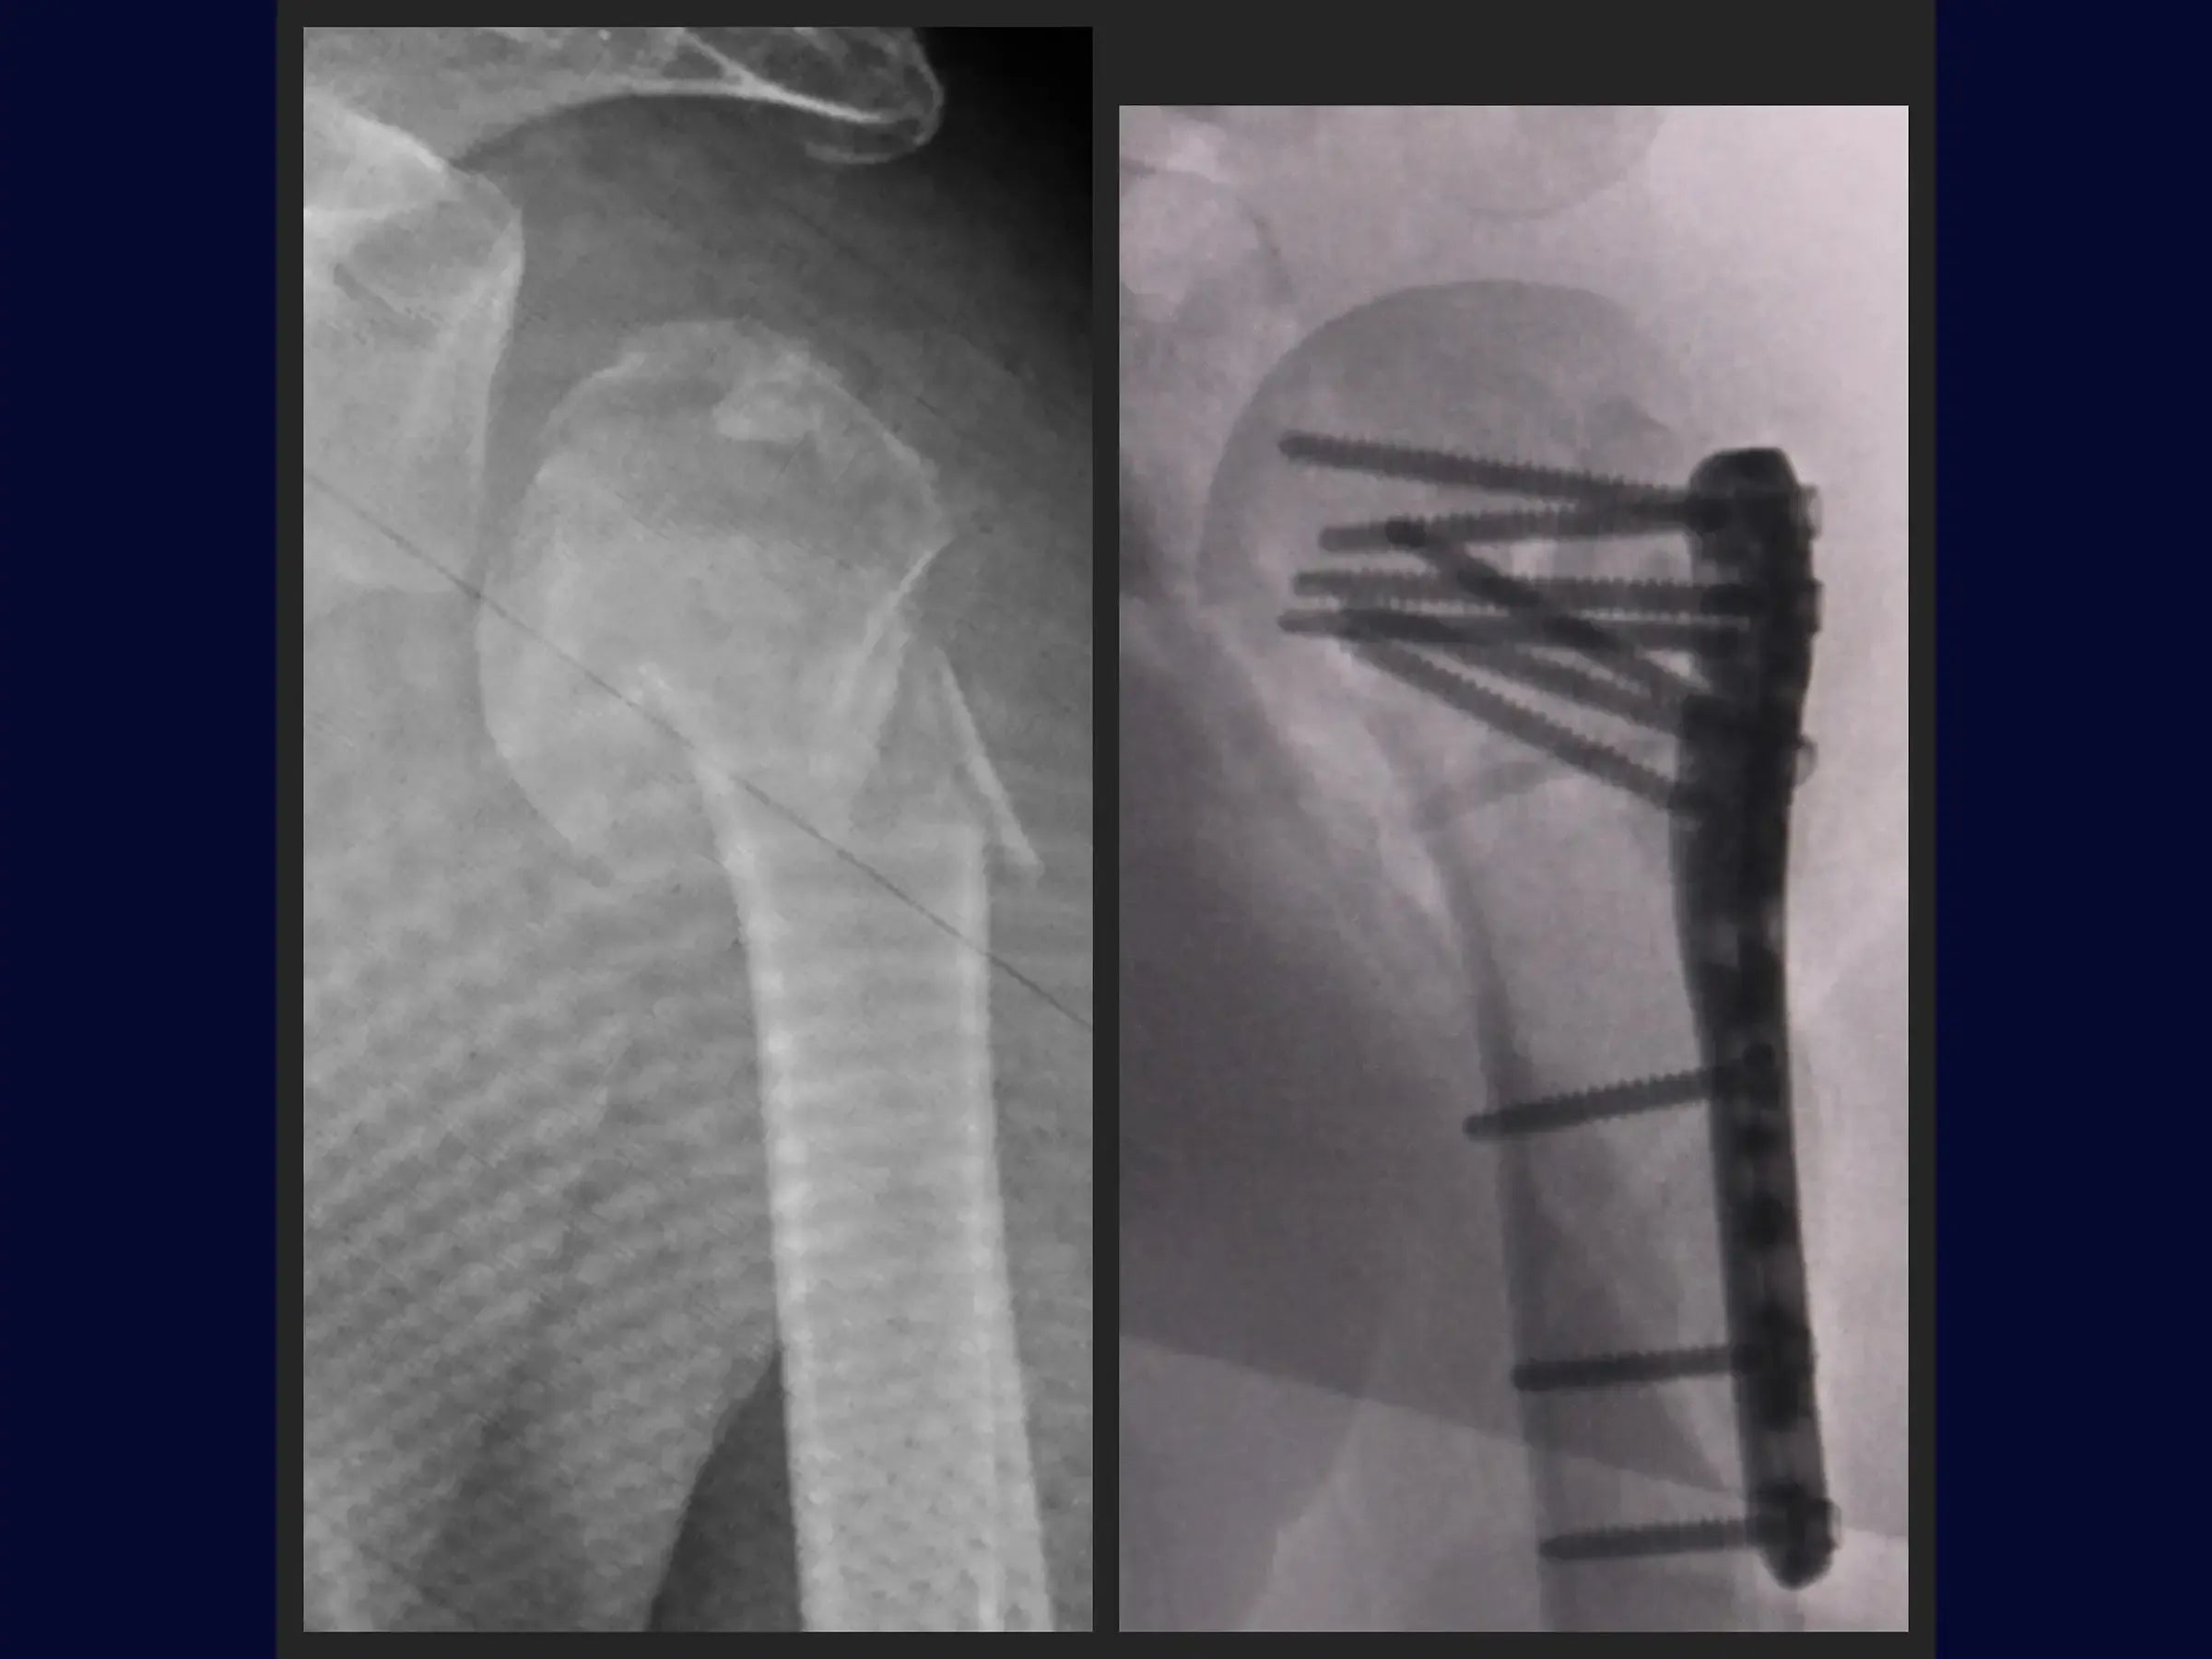

Domine o tratamento de fraturas complexas do úmero proximal. Este treinamento oferece uma imersão técnica na reconstrução de fraturas em quatro partes, com ênfase na abordagem deltopeitoral e fixação com placa e amarrilhas, apresentada em vídeo 4K sob a perspectiva do cirurgião.

- Reconstrução de fraturas complexas em quatro partes do úmero proximal.

- Fixação com placa e amarrilhas.

- Estratégias para Valgização da Cabeça Umeral: Abordagens para manipulação e valgização da cabeça umeral, incluindo o uso de fio de alta resistência e técnicas com broca e parafusos temporários para correção da impactação em varo.

- Posicionamento e Fixação da Placa: Princípios para posicionamento ideal da placa (1 cm lateral ao sulco bicipital) e inserção de parafusos, incluindo o parafuso dinâmico e parafusos no calcar para estabilidade e alinhamento.